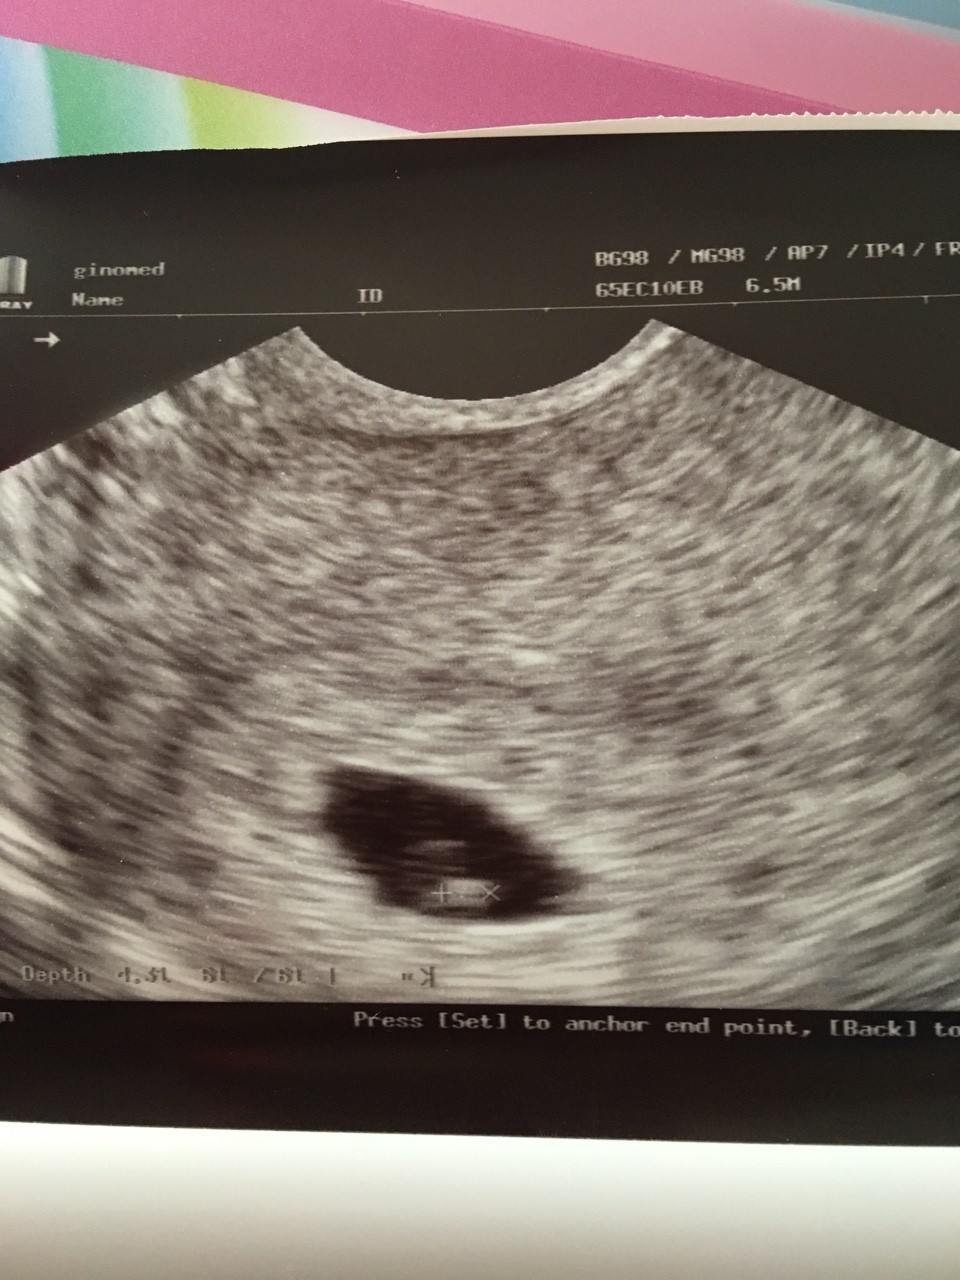

Mi to policzyła data ostatniej miesiaczki 15.04 + 7 to 22 i wyszło jej 22.01, a na zdjeciu usg jest podpisane na dole jak wychodzi wg sprzetu.Teraz ide 18 na wizyte i poprosze o wyliczenie. Wg aplikacji 29 stycznia mi wychodzi ale to wg aplikacji![]()

Mi to policzyła data ostatniej miesiaczki 15.04 + 7 to 22 i wyszło jej 22.01, a na zdjeciu usg jest podpisane na dole jak wychodzi wg sprzetu.

Na moim zdjęciu usg nie widac